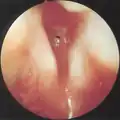

Subglottic stenosis is graded according to the Cotton-Myer classification system from one to four based on the severity of the blockage. Grade 1 is up to 50% obstruction, Grade 2 is 50-70% obstruction, Grade 3 is 70-99% obstruction, and Grade 4 is with no visible lumen.[5]

Grade 1 subglottic stenosis Grade 1 subglottic stenosis

Grade 2 subglottic stenosis Grade 2 subglottic stenosis

Grade 3 subglottic stenosis Grade 3 subglottic stenosis

Grade 4 subglottic stenosis Grade 4 subglottic stenosis